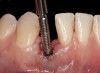

The crown and screw-retained custom abutment were removed, and a surgical cover screw was placed into the implant, thereby allowing spontaneous gingival augmentation in situ (Figure 33 and Figure 34). Note that the lingual aspect of the implant site was significantly more coronal than the labial aspect, which was positive because the defect would be limited to a facial–lingual defect. A fixed RBR bridge was cemented on the adjacent teeth and used as a tooth-supported transitional provisional restoration (Figure 35). A few weeks were allotted to let the soft tissue heal and migrate around the cover screw (Figure 36) to see if there would be complete coverage, thereby allowing a soft-tissue augmentation procedure to be performed with primary flap closure as in clinical scenario No. 2. The major obstacle in achieving a positive tissue response was that the implant depth was also deficient because the implant–abutment connection was at the level of the free gingival margin. It was decided that the best treatment option would be to remove the implant. A high-powered reverse-torque device (Fixture Remover Kit, NeoBiotech, www.neobiotechus.com) was used to remove the implant atraumatically (Figure 38 through Figure 41). The implant socket was allowed to heal for several months not unlike an extracted tooth (Figure 42). A new implant was placed in a better position from both a restorative and esthetic perspective (Figure 43), and after a few months of healing, a new crown was made (Figure 44). A satisfactory functional and esthetic result was achieved (Figure 45 and Figure 46) without employing pink porcelain.

Fig 33. Excessive facial angulation of the implant placement shown with an abutment driver in the access screw hole.

Fig 34. A surgical cover screw was placed in an attempt to decoronate the implant and gain soft-tissue coverage in situ.